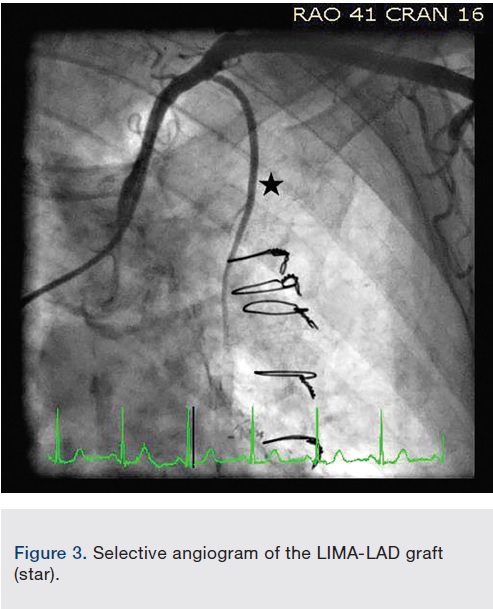

Right common femoral artery access was obtained, and selective coronary artery and bypass graft angiography performed. The right coronary artery (RCA) was proximally occluded (Video 1). The left main coronary artery demonstrated mild disease, with 100% occlusions of the mid left anterior descending (LAD) and left circumflex (LCX) coronary arteries (Figure 1, Video 2). Selective saphenous vein graft (SVG) to distal RCA angiography demonstrated a patent graft with a side-to-end anastomosis to the RV marginal artery, and distal anastomosis to the posterior lateral artery, which had mild disease (Figure 2, Video 3). Interestingly, there was also an end-to-end vein graft limb, originating mid graft, extending to an SVG to left posterior descending artery (LPDA). The SVG-LPDA graft was widely patent, and originated from the left internal mammary artery graft (LIMA) to LAD. The LIMA-LAD arose from the left subclavian artery, and had mild disease in the distal native LAD (Figure 3, Video 4).